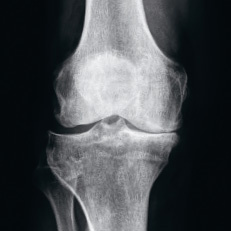

kniegelenkprothese_kunstgelenk

Abb. 7

Knie mit bestmöglich positioniertem Kunstgelenk.

Beim Eingriff bringt der Operateur die Schnittblöcke auf den entsprechenden Gelenkteilen an, wo sie der exakten Schnittführung dienen. Mit ihrer Hilfe wird die Oberfläche zugeschnitten, auf der die Prothese angebracht wird (Abb. 6–7). Der Chirurg kann so deutlich schneller und präziser arbeiten. Zudem fallen die für die Implantation nötigen Zugänge kleiner und gelenkschonender aus als bei älteren computerassistierten Operationstechniken. Für die Patienten bedeutet das weniger Schmerzen, weniger Blutverlust, eine grössere Beweglichkeit und einen kürzeren Spitalaufenthalt.